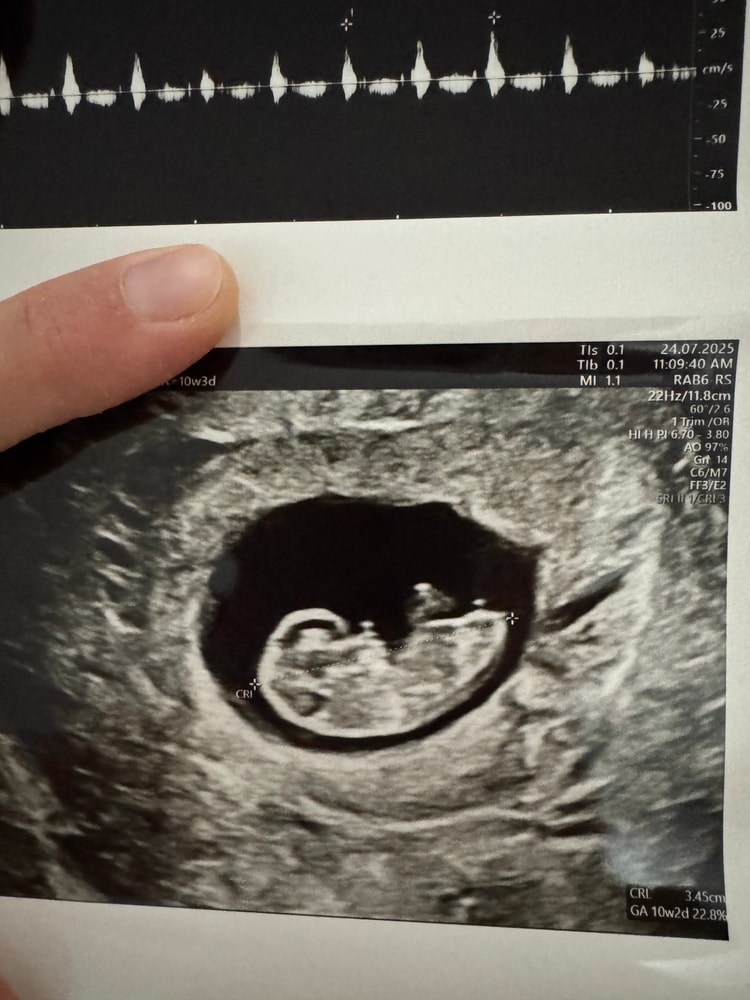

Узи 10 недель + 3 дня

Обратите внимание, что у меня идет только 11я неделя, а она во время узи на таком энтузиазме начала предполагать пол ребенка. Я не против, хотя сейчас во вторую беременность гораздо спокойнее относимся к тому кто у нас будет мальчик или девочка. И даже пробегала мысль может подождать с полом ребенка до родов. Но тут на узи такая хорошая видимость, что невозможно не обратить внимание.

В общем гинеколог думает, что это мальчик. Она говорит, что когда сама была беременна определила пол своего ребенка на 10 недель + 2 дня по углу. Я конечно знаю, что это все может быть сказки, но запишу сюда, чтоб в дальнейшем проверить 😁

В первую беременность на 12й недели врач гинеколог (другой, это было до переезда) предложил что у нас мальчик и уже через пару дней на скрининге нам сказали что это девочка. Так что может быть история повторяется?

Хотите присоединю фото с узи чтоб вместе погадать?